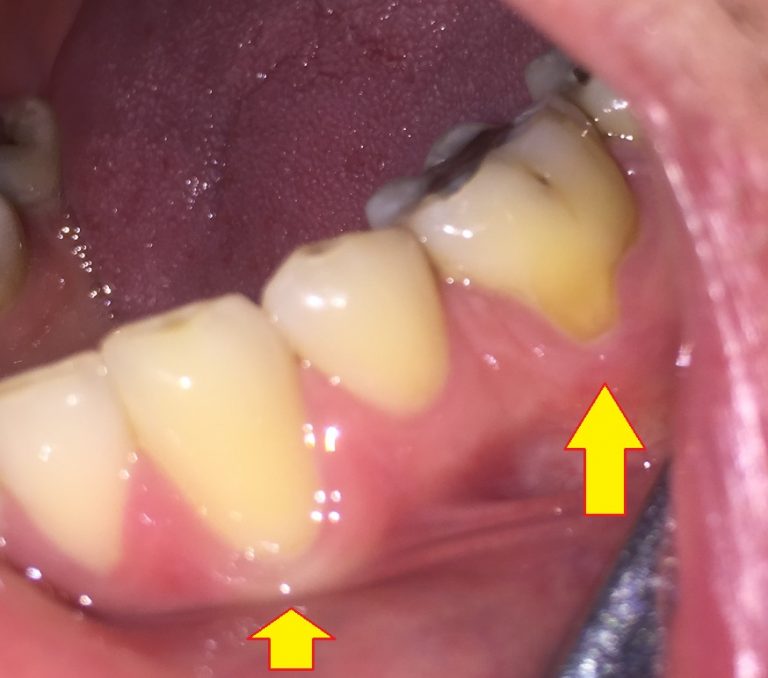

Souvent surnommé « furoncle dentaire », un petit bouton blanc sur la gencive est en réalité un abcès.Il est généralement causé par une maladie parodontale due à des bactéries qui se trouvent sur la gencive Il est essentiel de consulter un dentiste pour déterminer la nature exacte du bouton La gingivite: c'est une infection bactérienne de la gencive qui se manifeste au départ par des petits points blancs

Point blanc sur la gencive de bébé que signifietil et fautil s’inquiéter. Dans tous les cas, un bouton sur la gencive est un symptôme à prendre au sérieux, qui justifie de prendre contact avec votre dentiste pour obtenir un rendez-vous Il est essentiel de consulter un dentiste pour déterminer la nature exacte du bouton